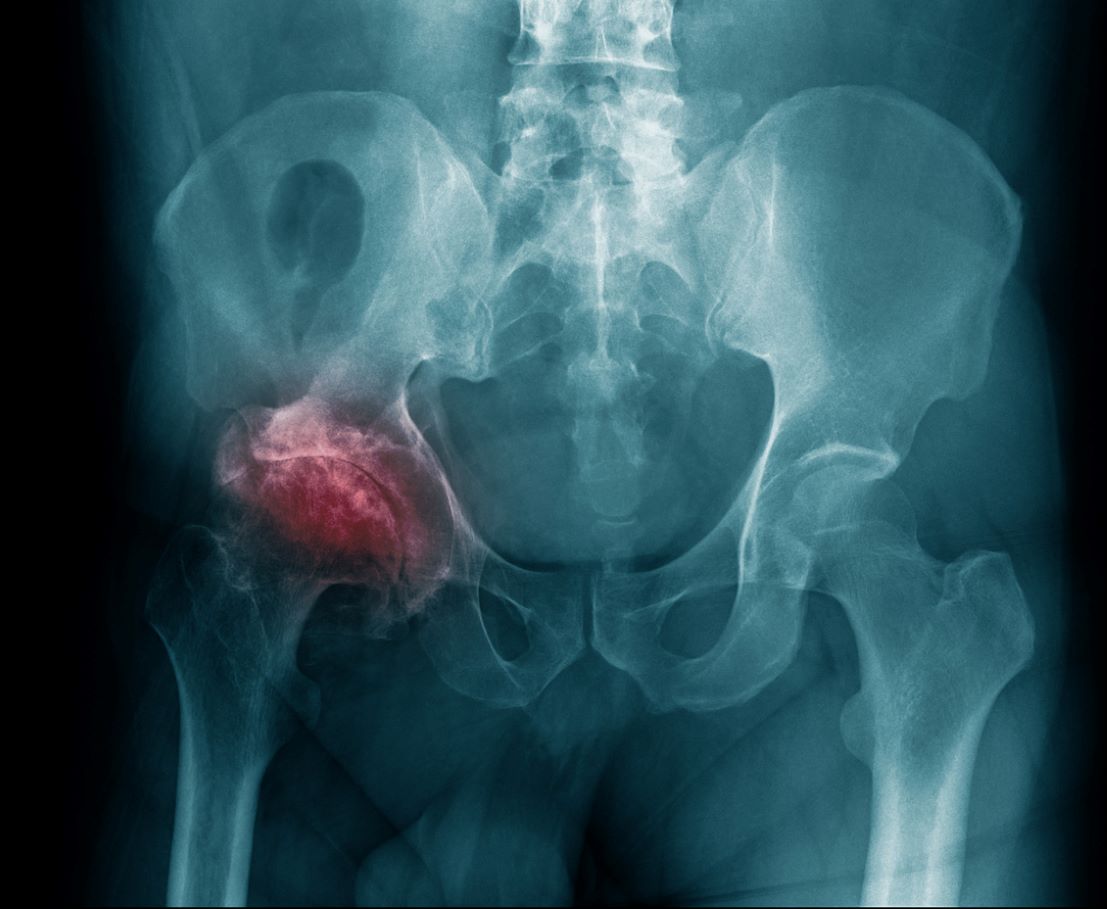

Η άσηπτη νέκρωση μηριαίας κεφαλής ή οστεονέκρωση μηριαίας κεφαλής, αποτελεί μια σοβαρή πάθηση του ισχίου, η οποία μπορεί να οδηγήσει σε καταστροφή της άρθρωσης και σημαντικό περιορισμό της κινητικότητας. Η έγκαιρη διάγνωση και η σωστή θεραπευτική στρατηγική αποτελούν καθοριστικούς παράγοντες για την πρόγνωση της νόσου. Αντίθετα, η καθυστερημένη αντιμετώπιση μπορεί να επιταχύνει την καταστροφή της άρθρωσης, οδηγώντας σε σοβαρό περιορισμό της λειτουργικότητας και συχνά στην ανάγκη για ολική αρθροπλαστική ισχίου. Στο παρόν άρθρο θα εξετάσουμε αναλυτικά τι είναι η άσηπτη νέκρωση μηριαίας κεφαλής, ποια είναι τα συχνότερα αίτια και συμπτώματά της, πώς γίνεται η διάγνωση και ποιες είναι οι σύγχρονες θεραπευτικές επιλογές για την αντιμετώπισή της.

Η άσηπτη νέκρωση μηριαίας κεφαλής είναι μια πάθηση που προκαλείται από τη διακοπή ή μείωση της αιμάτωσης στη μηριαία κεφαλή, δηλαδή στο άνω τμήμα του μηριαίου οστού που σχηματίζει την άρθρωση του ισχίου. Όταν η παροχή αίματος δεν επαρκεί, τα οστεοκύτταρα και ο οστικός μυελός υφίστανται νέκρωση. Η απώλεια της φυσιολογικής δομής του οστού οδηγεί σε μείωση της μηχανικής αντοχής της κεφαλής. Στα πρώιμα στάδια η άρθρωση μπορεί να παραμένει σχετικά λειτουργική, αλλά με την πάροδο του χρόνου το οστό αποδυναμώνεται, η επιφάνεια της κεφαλής χάνει τη σφαιρικότητά της και τελικά μπορεί να καταρρεύσει. Αυτό έχει ως αποτέλεσμα την παραμόρφωση της άρθρωσης, την εμφάνιση πόνου, προοδευτικό περιορισμό της κινητικότητας και σε προχωρημένα στάδια, την ανάπτυξη δευτεροπαθούς οστεοαρθρίτιδας του ισχίου.

- Απλή ακτινογραφία: Στα πρώιμα στάδια μπορεί να είναι φυσιολογική, αλλά σε προχωρημένα εμφανίζει αλλοιώσεις, όπως σκλήρυνση, κύστεις ή κατάρρευση της μηριαίας κεφαλής.